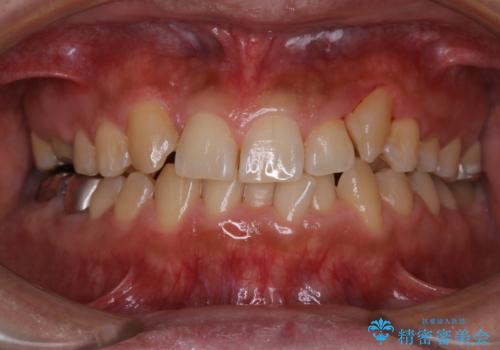

前歯メインにステインの付着が見られ、コース内容を相談した結果PMTC(保険外治療)の30分コースを行いました。